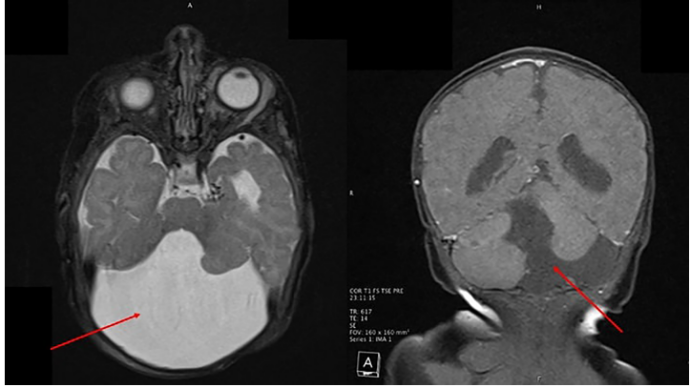

图3 头颅MRI影像

左面板(轴位)红色箭头示第四脑室囊状扩张;右面板(冠状位)红色箭头示后颅窝增大、小脑蚓部发育不全。